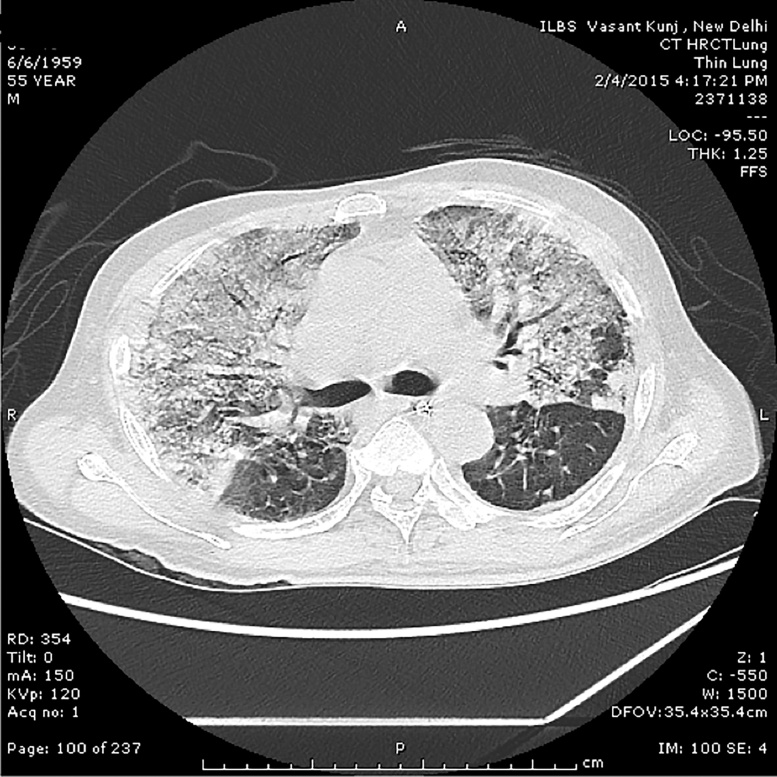

Figure 2.

High resolution contrast CT image of the chest showing dense consolidation in lung parenchyma merging into a background of widespread ground-glass attenuation. There is mild interstitial edema, more prominent at the lung bases.